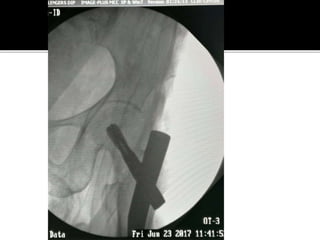

 CASE 1